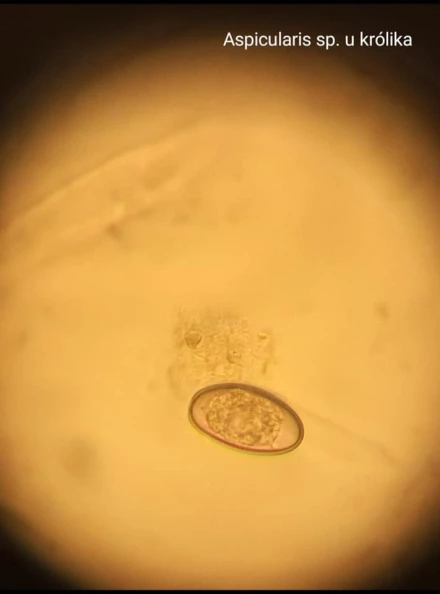

Diagnostyka chorób pasożytniczych

Choroby pasożytnicze są powszechnym problemem zdrowotnym u psów i kotów. Pasożyty mogą atakować różne układy organizmu, w tym skórę, przewód pokarmowy, układ oddechowy i krwionośny. Do najczęściej spotykanych pasożytów należą pchły, kleszcze, roztocza, nicienie, tasiemce oraz pierwotniaki. Regularne badania i profilaktyka, w tym stosowanie odpowiednich preparatów przeciwpasożytniczych, są kluczowe dla utrzymania zdrowia Twojego zwierzaka. Wczesne wykrycie i leczenie chorób pasożytniczych pozwala na uniknięcie poważnych komplikacji zdrowotnych. Oferujemy:

- Badanie kału: Przeprowadzamy badania kału, co jest kluczowe w diagnostyce pasożytów jelitowych.